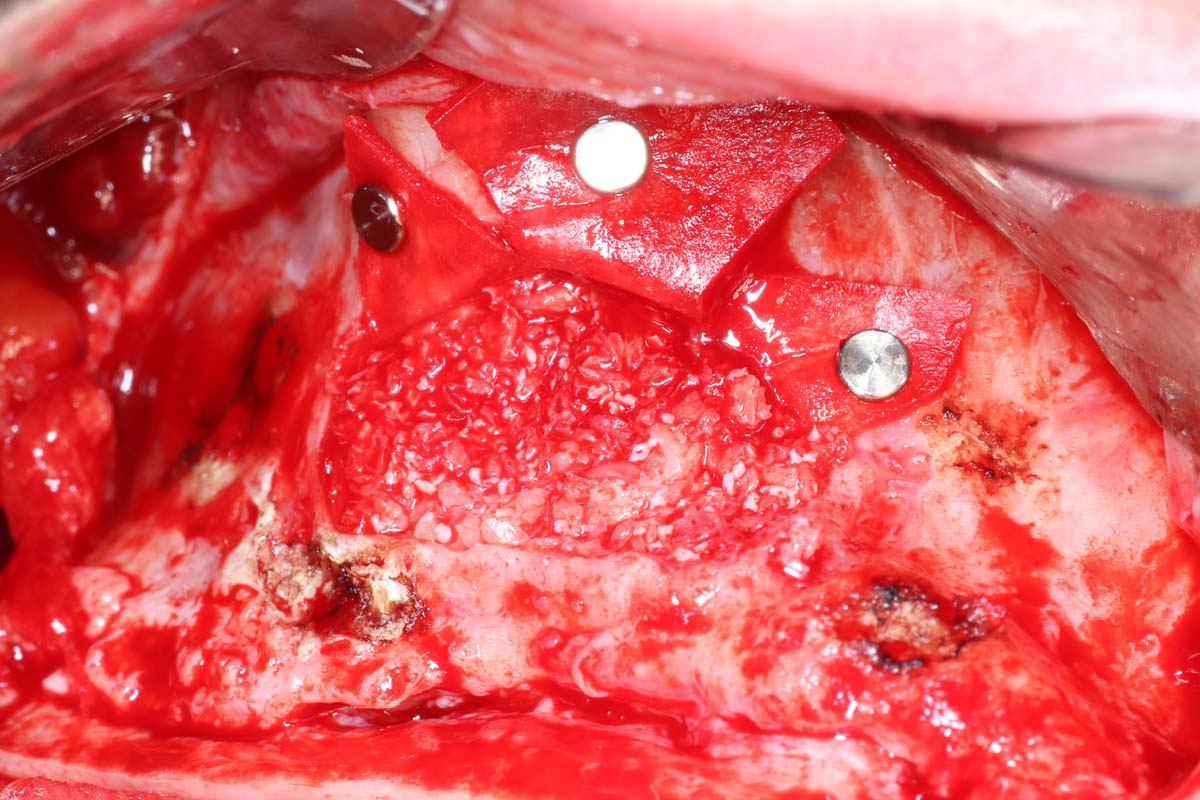

Gain insights from Dr. Pikos' extensive experience with over 1,600 sinus grafts. Discover successful techniques, common pitfalls, and nuances of grafting materials. Tackle complex cases and implement tips to ensure stability and integration for effective sinus augmentation outcomes.

Gain Hands-On Skills and Watch Live Surgery to Master Implant Site Development Techniques

Elevate your skills in implant site development with hands-on practice and live surgical demonstrations. Observe procedures in real time and participate in practical sessions to build confidence in essential techniques, from bone grafting to soft tissue management.

- Indications and step by step surgical protocol for sinus bone grafting – lateral and crestal approach.